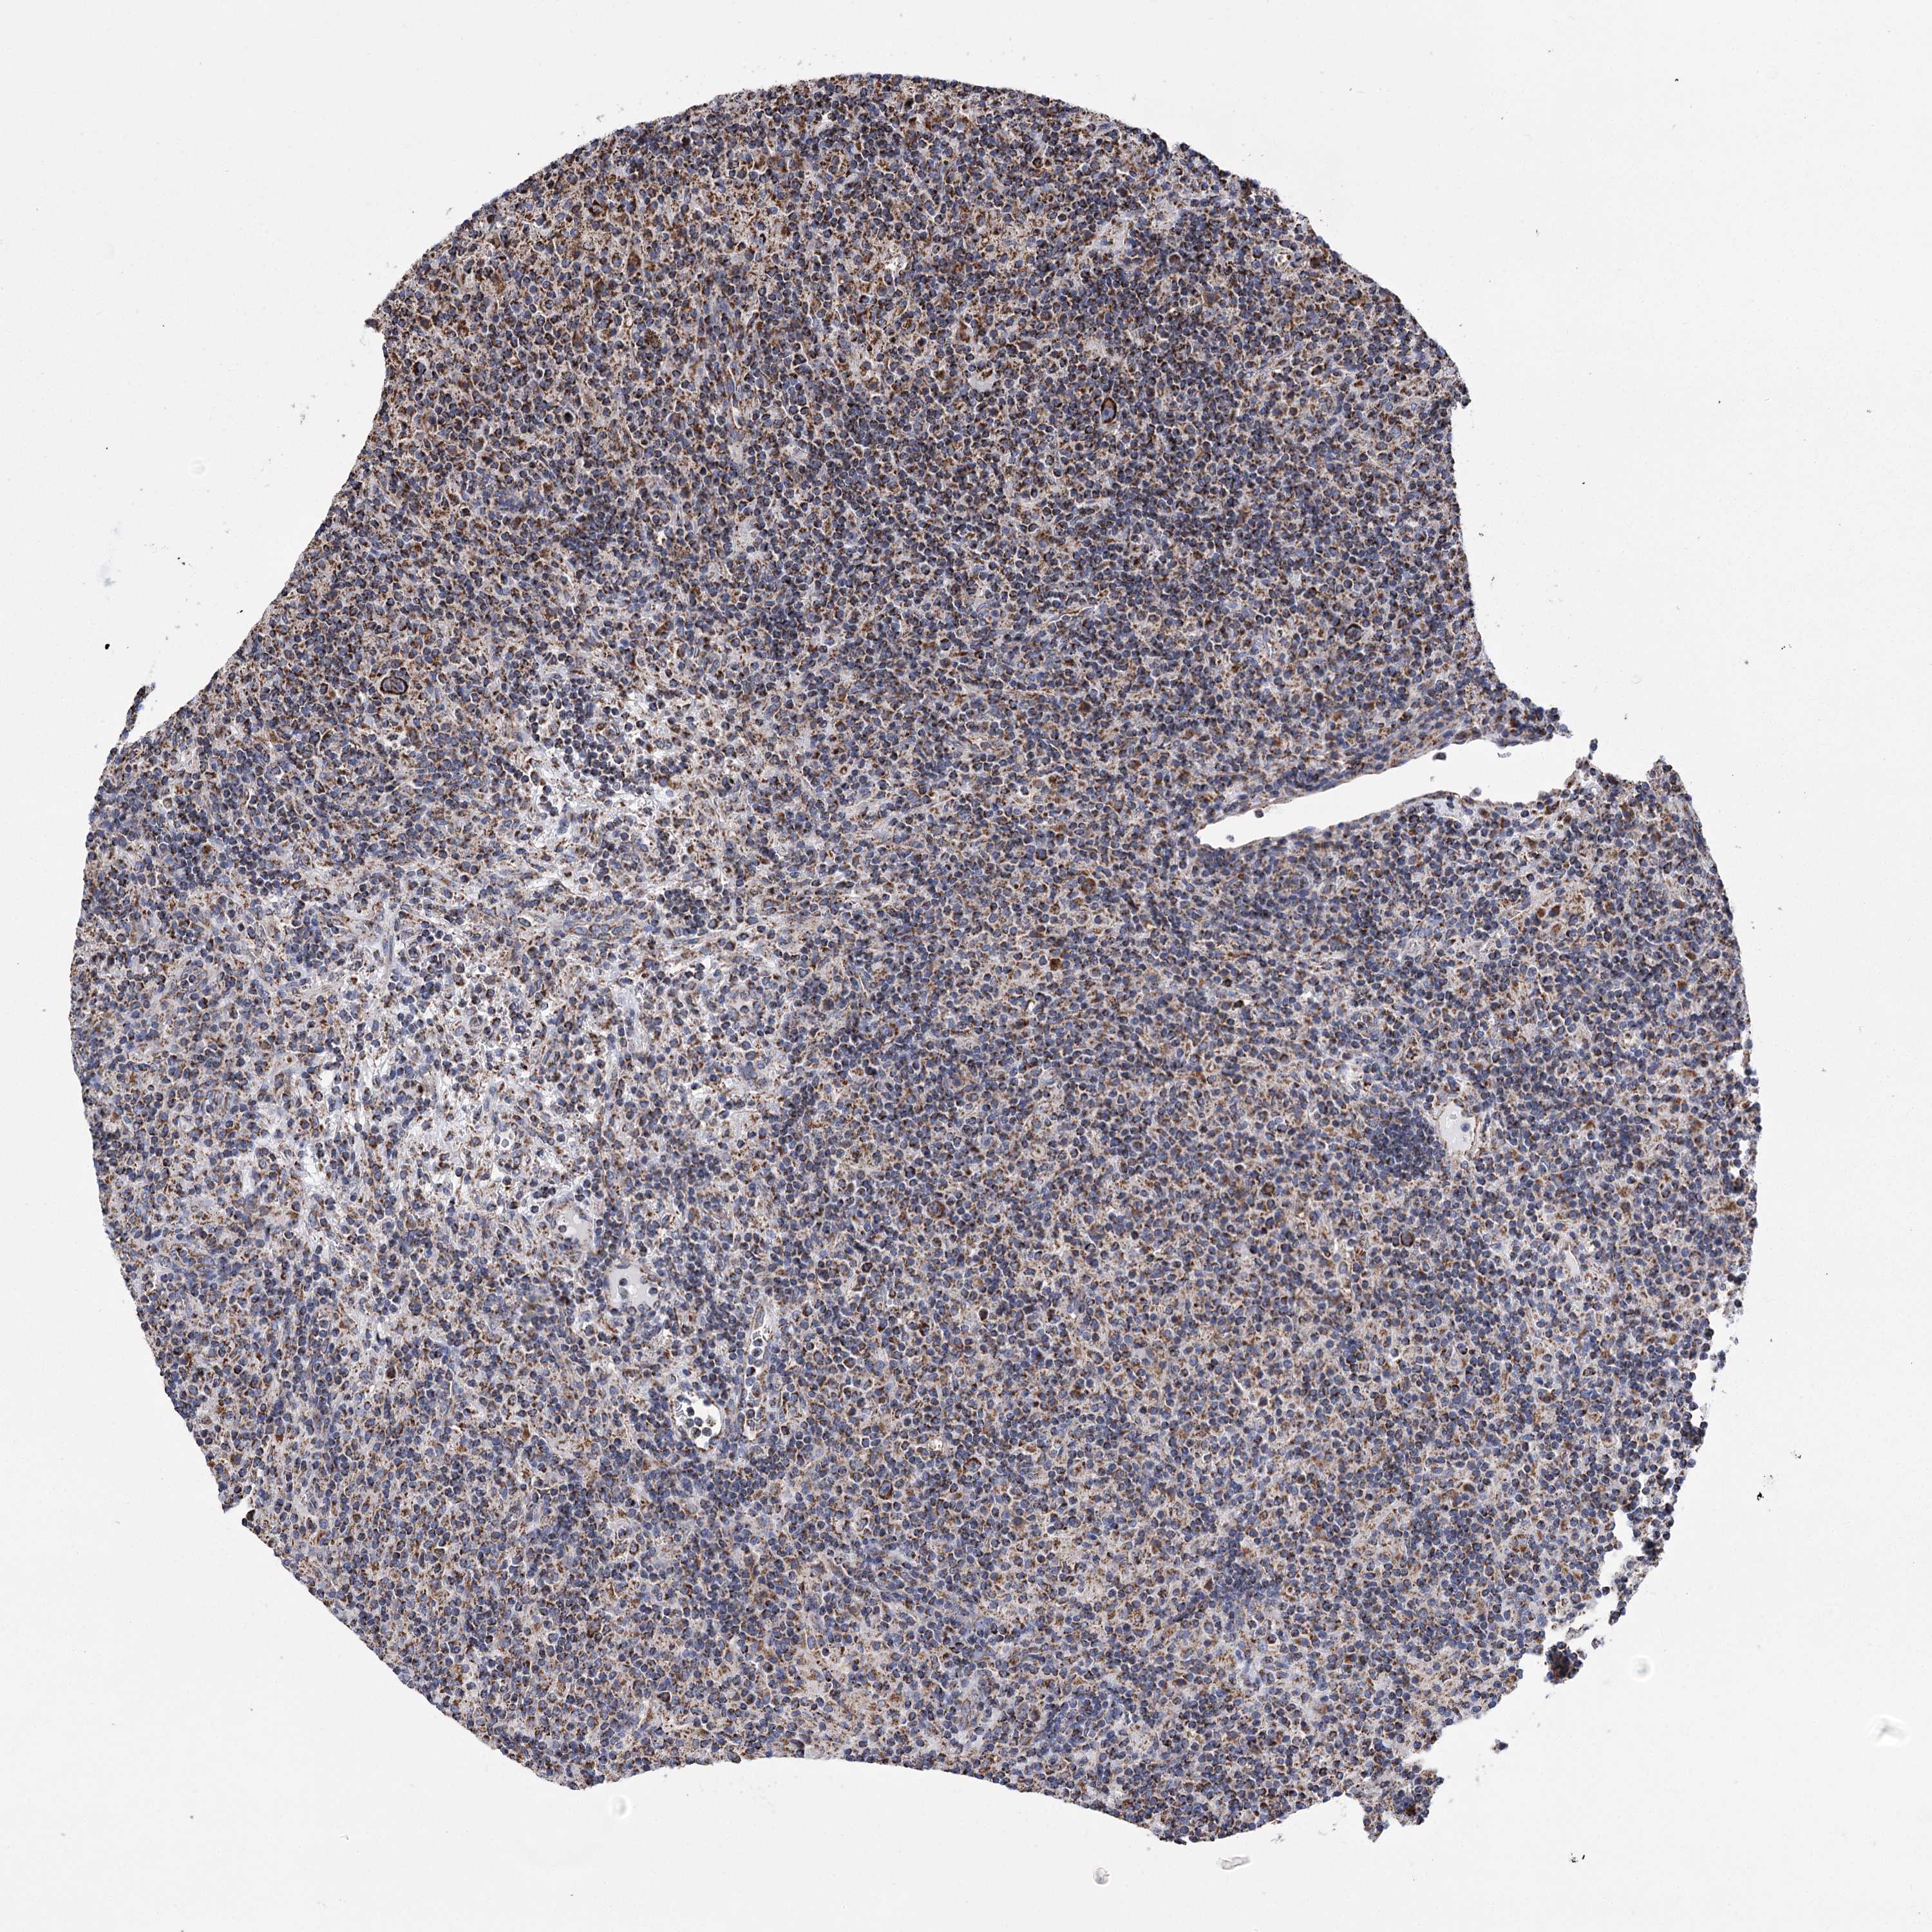

CANCER LYMPHOMA Show tissue menu

LYMPHOMA - Protein expressioni

A mouse-over function shows sample information and annotation data. Click on an image to view it in a full screen mode. Samples can be filtered based on level of antibody staining by selecting one or several of the following categories: high, medium, low and not detected. The assay and annotation is described here.

Each image is clickable and will lead to virtual microscopy that enables deeper exploration of all samples and also displays staining intensity scores, fraction scores and subcellular localization as well as patient and tissue information for each sample.

Antibody HPA038668

Antibody HPA038669

Hodgkin's disease, NOS

Malignant lymphoma, non-Hodgkin's type, High grade

Malignant lymphoma, non-Hodgkin's type, Low grade